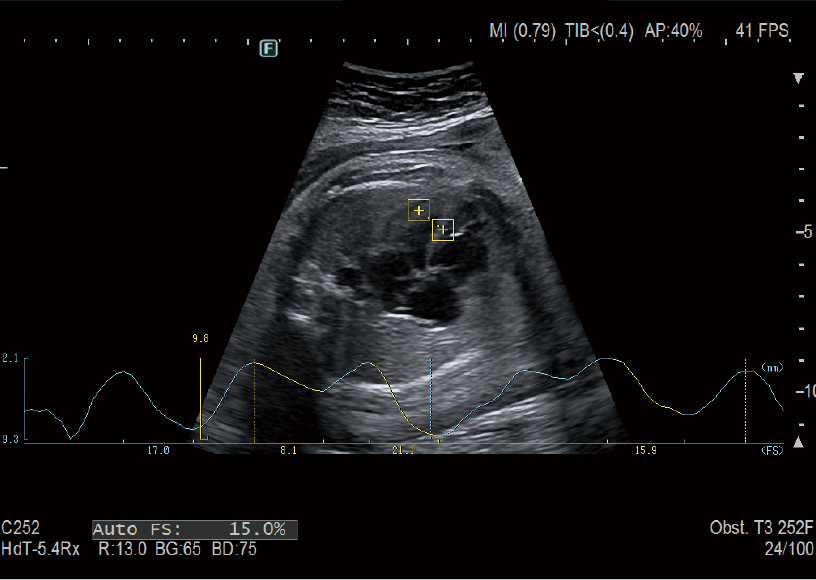

AutoFHR+ / AutoFS